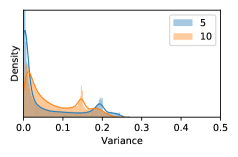

5.1 Distribution of Uncertainty Scores

Distribution of Uncertainty Scores Across Different Severity Levels As explained in Section 3, each uncertainty metric essentially defines an order/ranking among the data points. We conducted an analysis to better understand what data will be assigned high uncertainty under a particular uncertainty metric . Picking out the highest ranked data points (), we calculated the ratio of data points from each SL. Figure 4 summarizes the results as box plots for the Kaggle-DR and the Messidor-2 datasets; additional detailed statistics can be found in Table S.1 in the supplementary materials. From the plot and table, SL1 & SL2 examples account for a higher proportion among the top-ranked uncertain examples across the three ensemble methods. This finding matches our intuition that incipient disease examples (SL1 & SL2) are more likely to be considered uncertain by ensemble methods due to their ambiguity.

In contrast, the MC-dropout method showed the worst overall performance among the three, as it can be seen from the high ratios of SL0 examples among the uncertain negatives in Figure 4. The histograms in Figure 2 provides another perspective to look into the phenomenon, where a decent proportion of MC-dropout model’s predictions on SL0 inputs entailed low confidence (far from 0 or 1), which from another angle explained why MC-dropout was less specific in terms of lower FNP; many no-DR inputs (i.e. SL0) were erroneously assigned high uncertainty by MC-dropout models.

It is still an open question why the evaluated MC-dropout networks signaled relatively high uncertainty on SL0 & SL3 & SL4 data that are less likely to be ambiguous. We conjecture that much of the “uncertainty” indicated by disagreement among test-time dropout samples actually reflects the stochastic nature of dropout networks rather than the real decision uncertainty associated with the data. It is worth noting that the MC-dropout model we evaluated was not weak per se; they all achieved above Area Under Curve (AUC) scores on test sets. The weakness of individual test-time samples (which explains their low-confidence predictions on SL0 & SL3 & SL4) might have been hidden when they are aggregated into an ensemble—a well-known advantage of ensemble learning. Our results suggested that the uncertainty information given by implicit ensemble methods such as MC-dropout and TTA might not be as reliable as that from explicit ensemble approaches (e.g., stacking ensembles). Similar findings on MC-dropout can be found in some previous papers [1].

As discussed in Section 5.1 and Section 5.3 in the main paper, the mean metric and the stacking ensemble will have better performance in the precision (specificity) on the ambiguous data. Here, more detailed results are shown in Figures S.3 & S.6 and Table S.1. Figures S.3 & S.4 show the histograms of the uncertainty score for Kaggle-DR and Messidor-2 datasets that are the in-distribution (i.d.) dataset in our experiment and FigureS.5 & S.6 show the histograms for ImageNet and CIFAR-10 datasets, which is the o.o.d. datasets in our experiment. Each group of histograms contains results from the three evaluated ensemble methods (stacking ensemble, MC-dropout and TTA) and the three uncertainty metrics (mean, var and kl). Additional detailed results not displayed in Figure 4 can be found in Table S.1, which shows the proportion of the data of different SLs varies across different . For comparison, we also included in Table S.1 the results from single learners, and the proportions of data of different SLs (before any selection was made).